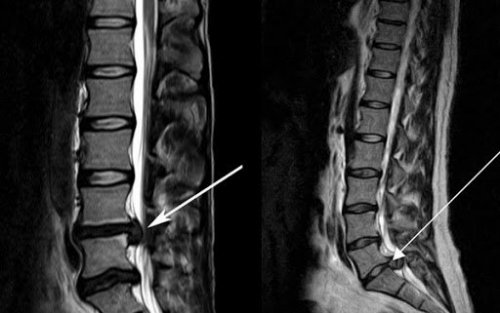

Грыжа диагностируется с помощью МРТ, КТ и УЗИ, при этом на рентгеновских снимках позвоночника такая патология видна редко. Существует еще и такое исследование для диагностики межпозвоночной грыжи, как миелография. Через прокол в позвоночный канал вводится контрастное вещество и проводится КТ или МРТ. Помните, что грыжа не определяется на ощупь, по симптомам или внешнему виду спины.